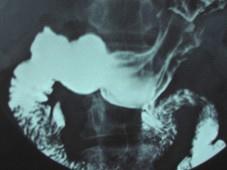

问题 女,23岁,上腹部疼痛半月,消化不良,X线检查如图,可能的诊断为 ( )

选项 A.十二指肠球部溃疡 B.十二指肠憩室 C.胃窦炎 D.十二指肠癌 E.十二指肠淤积症

答案 B